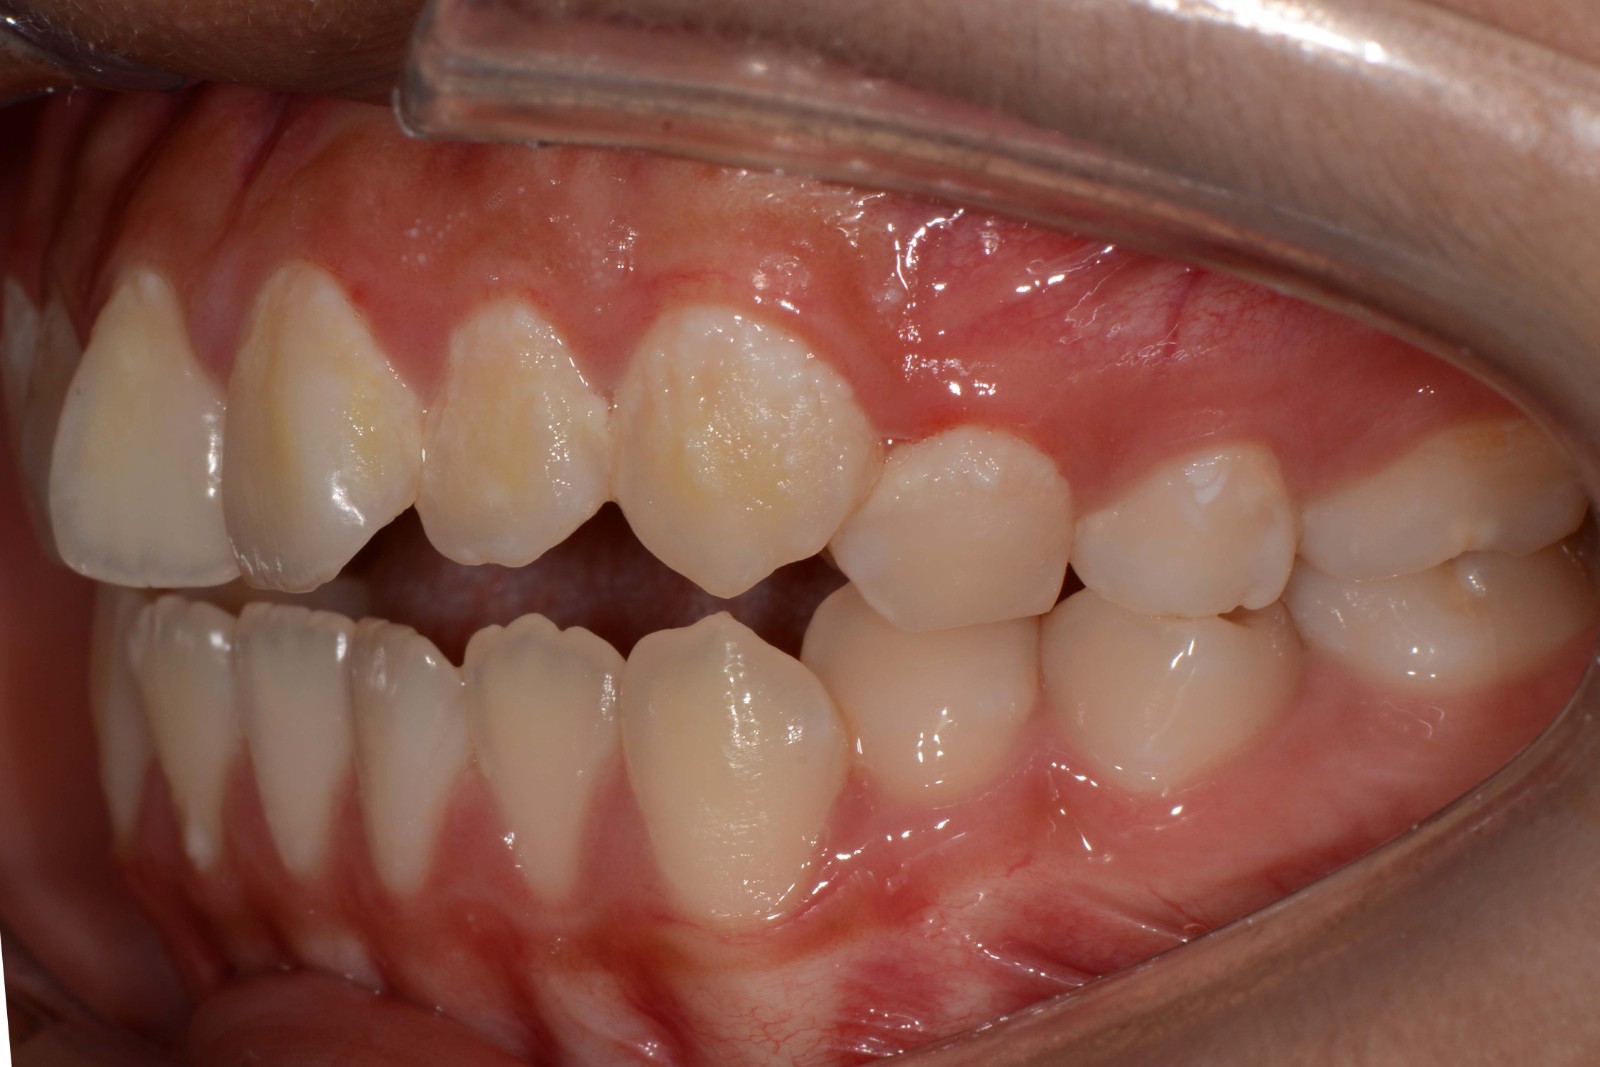

患者:14岁女性

诊断:安氏II类错颌畸形  开颌

治疗方案:拔除14 24 35 45,排齐整平牙列,调整覆合覆盖至正常,关闭间隙,精调,保持。

矫治前: